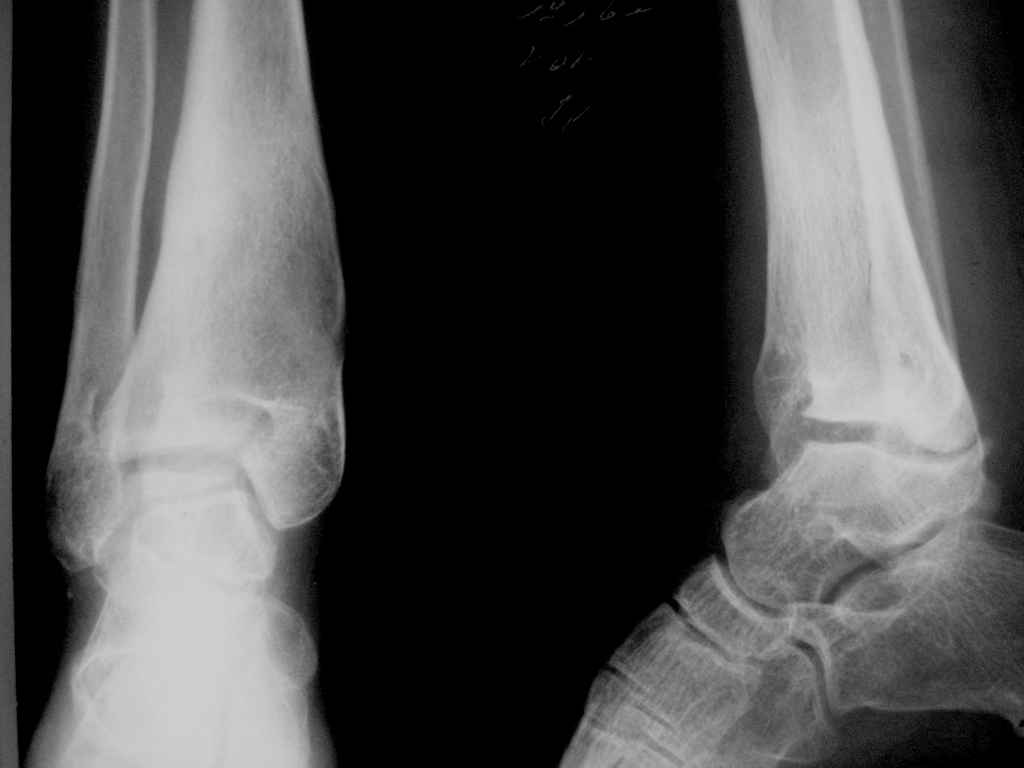

Девушка 17 лет: боли в голеностопном суставе,ограничение движений в суставе,укорочение голени,хромота Из анамнеза в раннем детском возрасте перенесла гематогенный остеомиелит дистального отдела большеберцовой кости - зона роста частично закрылась сформировалась варусная деформация голеностопного сустава + укорочение костей голени на 6 см Произведена корригирующе-удлиняющая остеотомия сначала большеберцовой,затем малоберцовой костей, устранена деформация, ликвидировано укорочение. С возрастом наросло укорочение до 3 см,клинически умеренная вальгусная деформация голеностопного сустава. Объём движений в суставе в пределах 15 град. Отмечает переодически болевой синдром, после осевой перегрузки,пользуется обувью с компенсацией, ортезом на голеностопный суставВопрос: есть ли показания для оперативного лечения: артропластика? артродез? голеностопного сустава. Какие мысли,коллеги?